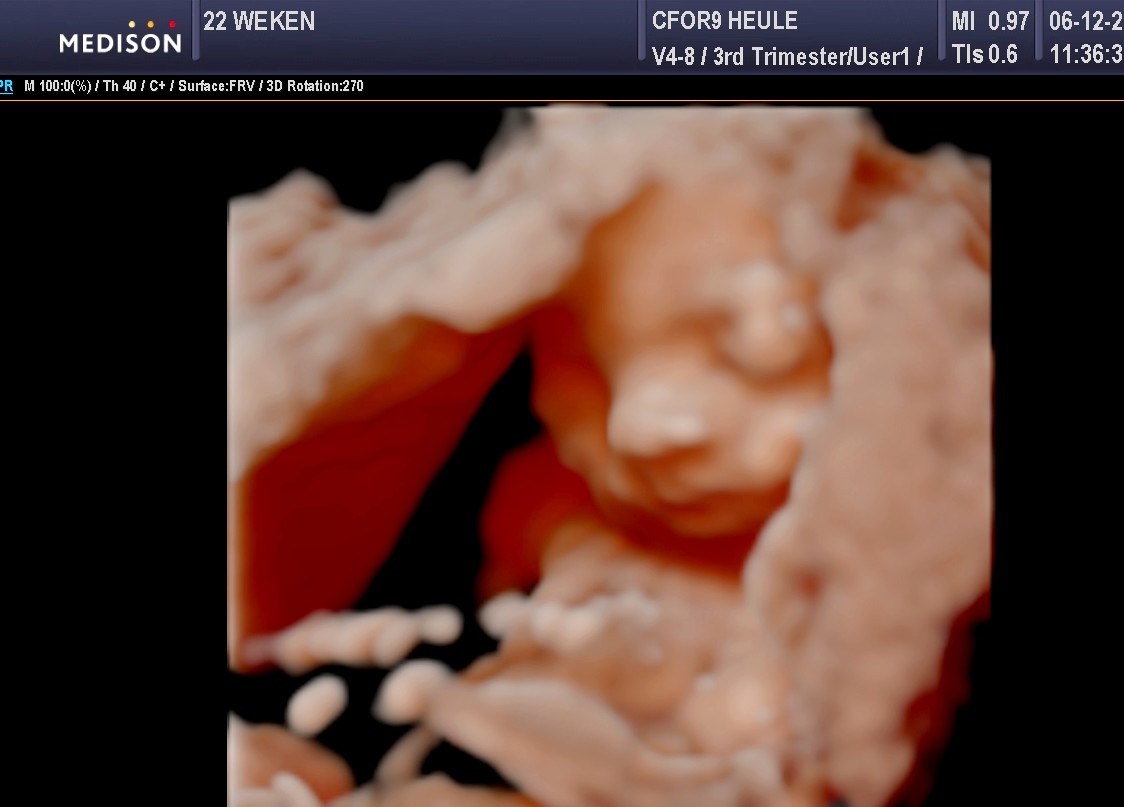

Mama en papa geven elkaar geen cadeautjes op Valentijn, maar dit jaar kozen we ervoor om deze feestdag toch een vrolijk kleurtje te geven door een extra bezoekje aan Cfor9. Je gelooft het echter misschien niet, maar jouw hoofdje was terug zo gedraaid dat we jou niet konden zien. Je staat precies even graag op de foto als jouw papa… niet dus (knipoog)!

Op 21 februari 2015 hadden we dan ook een nieuwe afspraak bij Sylvie. In plaats van jou nog eens te zien bij 32 weken zwangerschap konden we je nog even bewonderen bij 33 weken zwangerschap. Amai, wat ben je veranderd in vergelijking met de vorige keer. We zien echt dat je goed groeit. Vooral jouw bolle kaakjes vinden we zo schattig. Op het eerste zicht heb je trouwens de neus van de mama en de lipjes van de papa. Wat kijken we ernaar uit om jou te kunnen knuffelen!

Dit waren jammer genoeg wel de laatste 3D-beelden die we zullen kunnen zien van jou tijdens de zwangerschap. In het ziekenhuis maken ze enkel een 2D-echo en omdat je meer en meer met jouw hoofdje in mama’s bekken daalt zal Sylvie geen foto’s meer van jou kunnen maken.